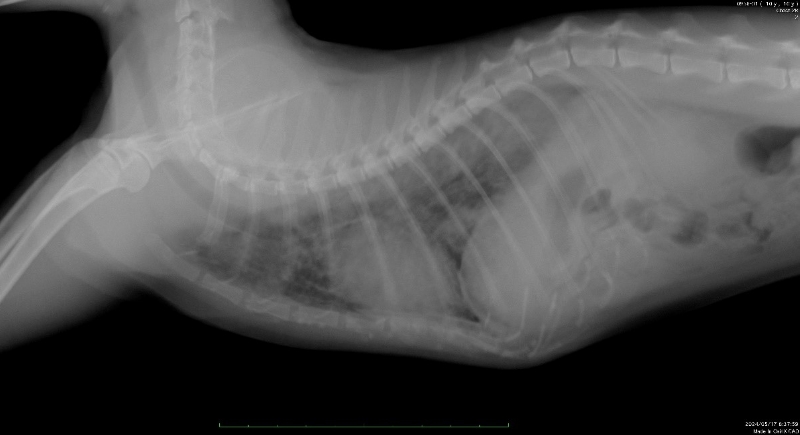

僧帽弁閉鎖不全症と肺水腫

ワンちゃんで最も多くみられる循環器疾患で、特に中年齢以上の小型犬に多く認められます。

心臓の左心房と左心室の間にある逆流防止弁がうまく閉まらなくなり、血液が左心室から左心房へ逆流を起こします。これにより心臓へ負荷がかかるとともに肺から心臓に入る血液の流れにも支障が出てきます。

そうすると肺で鬱血(血の流れが滞る)状態になり、血液の水分が肺の空気の入る部分に滲み出てしまい、肺胞に水が溜まる肺水腫になります。

このようになると咳と呼吸困難が見られ、危険な状態になります。

胸部レントゲンやエコー検査などを実施し、適切な治療をすることで、症状の改善や健康寿命を延ばすことができるので早期発見早期対応が大切です -